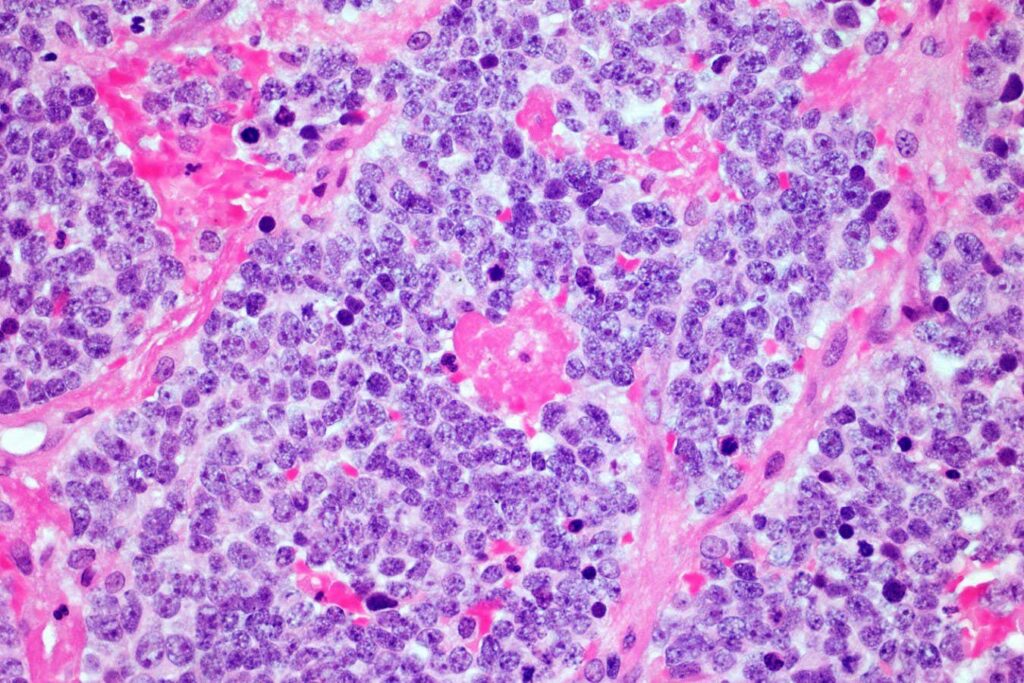

Microscopic images of neuroblastoma tumors

However, CAR T-cell therapy usually fails against solid tumors such as neuroblastoma. Neuroblastoma occurs when developing neurons in children and usually becomes cancerous before the age of five. Such tumors often resist being attacked by the immune system, reducing the effectiveness of the modified T-cell.